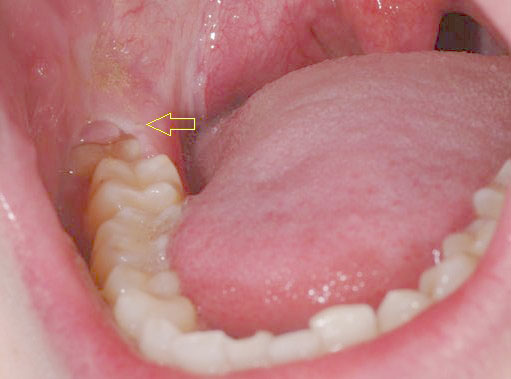

Khi nào nên nhổ răng số 8?

Câu hỏi: Chào bác sĩ Hoàn Mỹ. Mấy ngày gần đây, chỗ phía răng hàm của em đau nhức dữ dội, khi em soi vào thì thấy có hai chiếc…